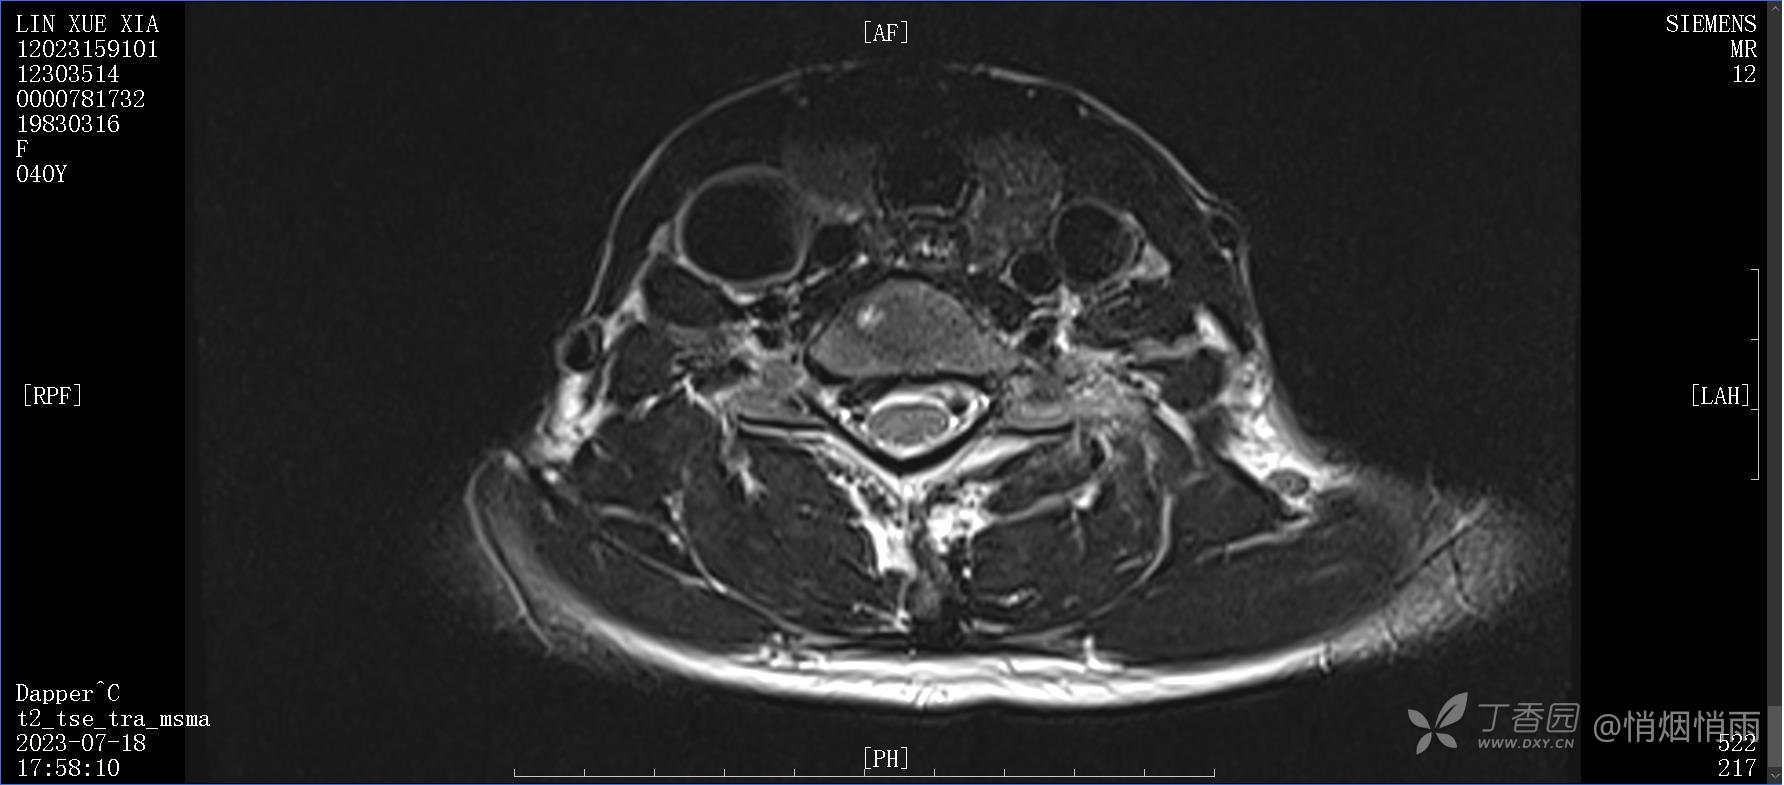

NeurothinkerZ 推荐患者女性,40岁,因右肩背部疼痛班活动受限4日余入院(2023-07-17)。

病史:入院前4天无明显诱因突然感右肩背疼痛伴随活动受限,自行口服依托考昔、艾瑞昔布等药物治疗,院外应用肩关节局部手法按摩等,均无明显改善。外院门诊诊为颈椎病。自诉既往多次“胸椎小关节紊乱”于当地诊所行手法按摩,治疗后好转,否认慢性疾病病史、外伤史、手术史,诉青霉素过敏,无其他药物食物过敏史,否认吸烟史、饮酒史,月经正常,经量正常。

查体:右肩关节局部轻度肿胀,肩胛区压痛明显,痛处不固定,肩关节痛性活动受限,jobe test(+),lift -off test(+),中指、环指感觉较余指减退,余肢端感觉及血运情况可。

目前的诊断,暂时依据辅助检查诊为肩袖损伤,但是患者疼痛的性质和特点,却不是单纯的肩袖损伤所致。考虑过胸廓出口综合征,但是该疾病会出现肩胛区的疼痛吗?(由于考虑到费用的问题,没再进行下一步的检查)带状疱疹会有如此的症状吗?